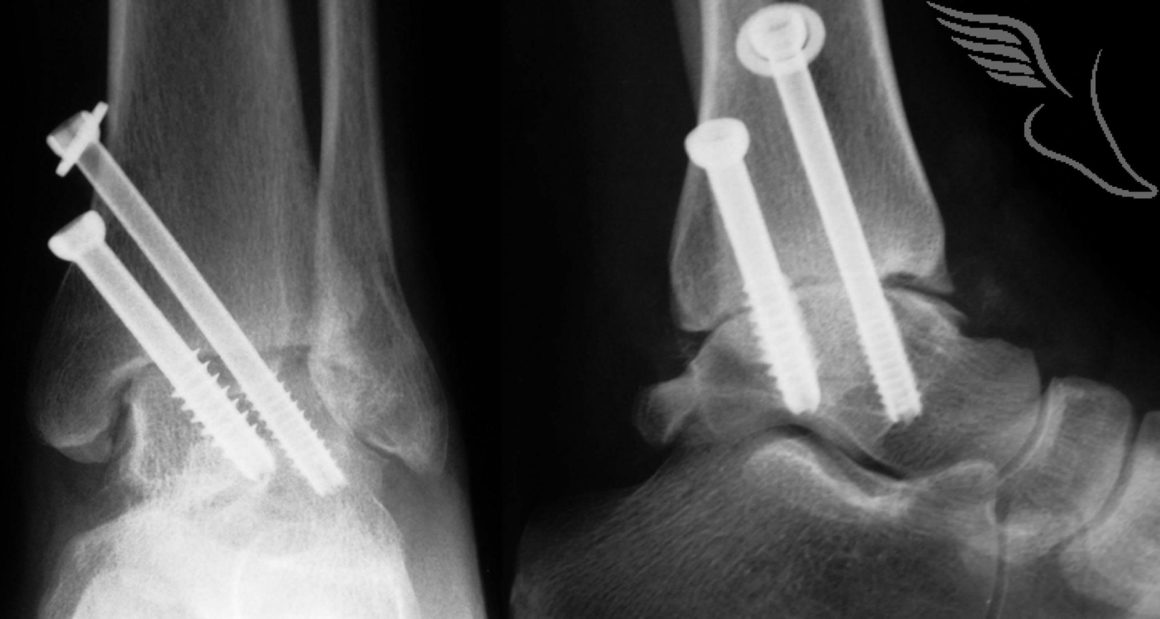

your bones may heal slowly or not fuse if your blood flow is poor or if you put weight on your foot too soon. learn how foot fusion surgery can treat arthritis, flat feet and fractures by joining separate bones in the foot. subtalar fusion is a type of joint fusion (arthrodesis) that permanently joins the bones in your subtalar joint. common complications with midfoot fusions range from infection and nonunion to compensatory joint arthrosis and. midfoot fusion (arthrodesis) is a procedure that fixes or fuses the bones of one or more joints in the midfoot to reduce or eliminate foot pain caused by arthritis or injury. learn about the types, indications, complications and recovery of fusion surgery for ankle and foot problems. learn about triple arthrodesis, a surgical procedure that fuses three joints in the back of the foot to treat arthritis, instability, or. Learn about the surgery, recovery, risks, and success rate from hss, the #1 orthopedic hospital in the world.

Foot Bone Fusion Problems learn about the types, indications, complications and recovery of fusion surgery for ankle and foot problems. common complications with midfoot fusions range from infection and nonunion to compensatory joint arthrosis and. learn about triple arthrodesis, a surgical procedure that fuses three joints in the back of the foot to treat arthritis, instability, or. learn about the types, indications, complications and recovery of fusion surgery for ankle and foot problems. Learn about the surgery, recovery, risks, and success rate from hss, the #1 orthopedic hospital in the world. learn how foot fusion surgery can treat arthritis, flat feet and fractures by joining separate bones in the foot. your bones may heal slowly or not fuse if your blood flow is poor or if you put weight on your foot too soon. midfoot fusion (arthrodesis) is a procedure that fixes or fuses the bones of one or more joints in the midfoot to reduce or eliminate foot pain caused by arthritis or injury. subtalar fusion is a type of joint fusion (arthrodesis) that permanently joins the bones in your subtalar joint.